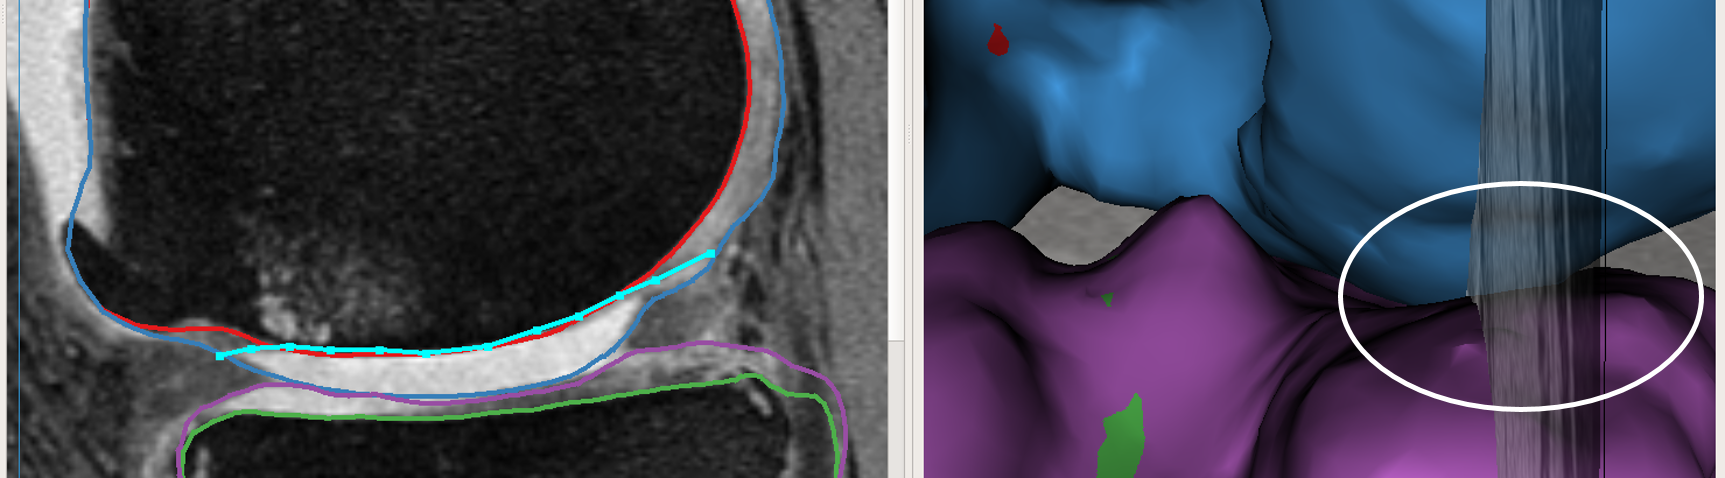

Max-flow re-computation: Following the local graph cost modification the max-flow is recomputed in 3D within a few milliseconds and the updated surfaces rendered onto the GUI. As seen in Fig. 3b the correction made by the nudge points are reflected in the updated cartilage surface overlayed on the image volume.

The above work-flow is repeated to correct the tibial cartilage errors as well. In the intermediate steps following the correction of the femur, the tibia bone and cartilage surfaces appear to worsen. This can be attributed to a combination of the existing graph costs and the graph constraints. Since the tibia cartilage surface has no clear defined edge cost in that region, the surface result moved along with the femur corrected cartilage surface. Subsequently due to the inter-surface distance constraints between the tibial surfaces the tibial bone surface also changed. However once the nudge points provided the appropriate locations for cost modification the erroneous surfaces were corrected (Figs. 3c,d). Note that the corrections made on a single 2D slice resulted in the entire locally affected 3D neighborhood being corrected. This can be appreciated in the corresponding circled regions of the surface model.